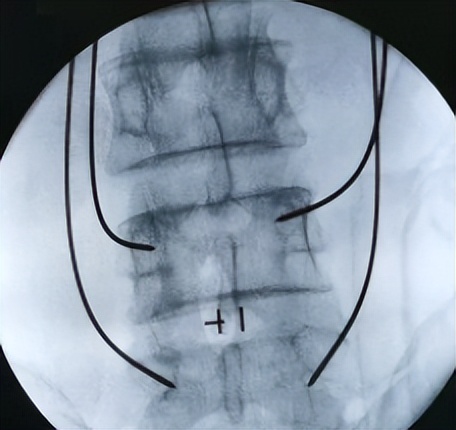

术中

这时候再结合骨科机器人,根据术前规划路径,自动调节进针角度、分析确定定位点,并智能自动寻找。在骨科机器人的帮助下,医生只需在置钉部位切开约2cm切口,这样不损伤其它椎关节,保障了神经安全。